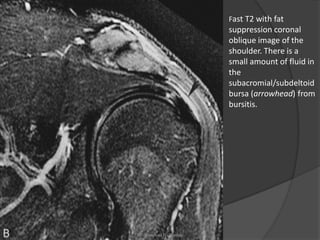

Fast T2 with fat

suppression coronal

oblique image of the

shoulder. There is a

small amount of fluid in

the

subacromial/subdeltoid

bursa (arrowhead) from

bursitis.